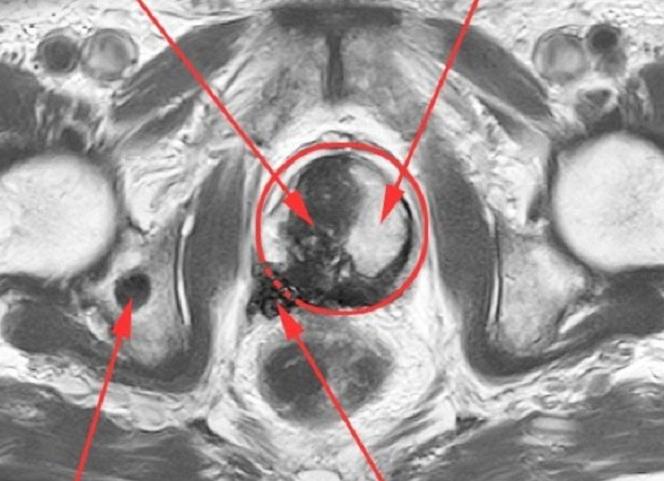

Патологии простаты

Данное МРТ предстательной железы проводится введением контрастного вещества через инъекцию внутривенным путем. Это дает хорошую различаемость на мониторе аппарата. Такой осмотр позволяет рассмотреть здоровую и пораженную ткань. Назначение о проведение исследования контрастом принимается профильным специалистом, в случае если у мужчин есть подозрения на онкологический процесс предстательной железы.